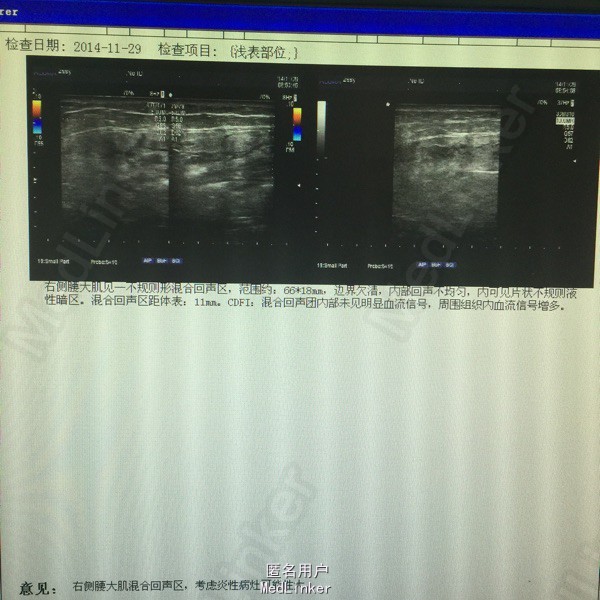

男,41岁,反复右侧腰部疼痛3。患者3月前出现右腰部疼痛,伴低热,就诊当地医院,超声提示腰大肌脓肿,给予穿刺引流,抗感染治疗。同时活检病理无特殊。现疼痛来我院。

局部皮肤完整,右侧腹部肌紧张,压痛明显,反跳痛阳性。

行脓肿切开引流术,术中见 牙签一枚!术后一周拔除引流管,复查脓腔缩小,无发热无疼痛。

患者不明原因导致牙签滞留体内,反复发热疼痛,影像检查未发现,排除结核感染。及时手术是最佳治疗。